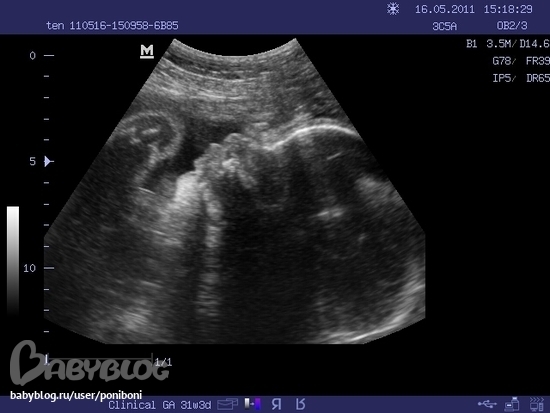

Нам тут 3 месяца